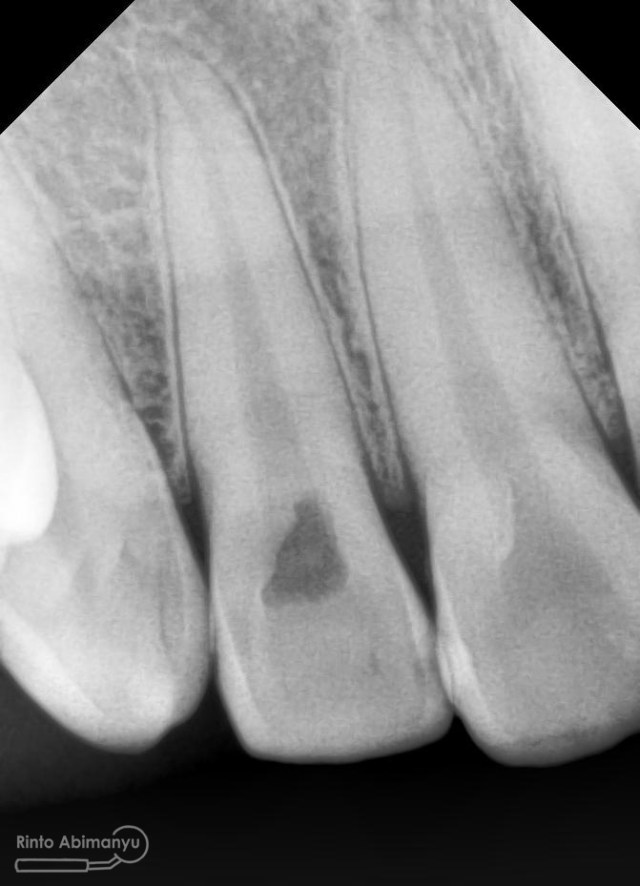

Prosedur sama seperti kemarin memasangkan rubber dam dahulu untuk isolasi daerah kerja, kemudian melakukan akses ke kamar pulpa… Penjajakan awal saluran akar menggunakan K-file nomer 10, dan panjang kerja diukur menggunakan apex locator… Irigasi dan aktivasi masih menggunakan metode yang sama juga… Setelah prosedur cleaning and shaping selesai dilakukan pengepasan guttap dan difoto ronsen…

Foto radiografis trial guttap gigi 22

Nah dari foto ronsen ini juga saya melakukan evaluasi hasil pengisian pada gigi 11 21 nya… alhamdulillah pengisian yang kemarin terlihat sepanjang kerja dan padat serta rapat… Pada gigi 22 nya pun pengepasan guttap terlihat sudah sepanjang kerja…